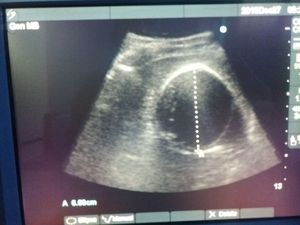

You have too know this !!!!!!

Radiology

Spleen

Ultrasound

Ehinocok

Ecinococus granolosus